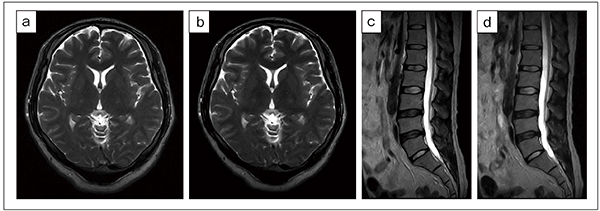

まず,ノイズ除去強度(Light,Medium,Heavy)によりSNRはどのように変化するのでしょうか。頭部と腰椎の撮像条件において,ノイズ除去強度を変えて各SNRを測定しました。頭部ではT2強調画像(T2WI),T1強調画像(T1WI),FLAIR,腰椎ではT2WI,T1WI,STIRの画像種を想定しています(図1)。

IP-Reconを使用していない画像と比較してLight,Medium,Heavyとノイズ除去強度を上げるに従い,SNRは増加しました。撮像条件によりSNRの増加量は異なりますが,増加量が大きかった頭部T1WI(図1 b)では,Light:142%,Medium:162%,Heavy:201%という結果になりました。このことから,IP-Reconにおけるノイズ低減によりSNRは増加し,さらにノイズ除去強度を変えることでSNRの増加量を段階的に調整できるということがわかります。

図1 IP-Reconの強度によるSNR変化

a:頭部T2WI:TR/TE=4900/120,スライス厚:5.0mm,撮像時間:4:01

b:頭部T1WI:TR/TE=500/10.7,スライス厚:5.0mm,撮像時間:4:50

c:頭部FLAIR:TR/TE=8000/90,スライス厚:5.0mm,撮像時間:5:05

d:腰椎T2WI:TR/TE=2700/100,スライス厚:4.5mm,撮像時間:5:03

e:腰椎T1WI:TR/TE=440/14,スライス厚:4.5mm,撮像時間:4:58

f:腰椎STIR:TR/TE=2700/80,スライス厚:4.5mm,撮像時間:5:54